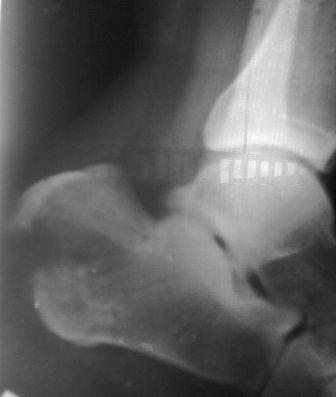

Здравствуйте, уважаемые коллеги. Обратился больной 29лет, через 25 дней после травмы с переломом обеих пяточных костей, слева без смещения, справа внесуставной отрывной перелом бугра пяточной кости (утиный клюв) в гипсовой повязке.

После снятия гипсовой повязки в обл. смещенного бугра имеется некроз м/тканей с образованием тонкой плотной корочки, спаянный с костью.

Честно сказать, пока не знаю что делать, если даже мимо некроза вводить стержень Щанца и попробовать опустить "клюв", рвется некроз с оголением кости, может присоединится инфекция,и остеомиелит на всю жизнь. Если по методу Илизарова, тоже может быть такая же история.

Если не трогать, то болезненная деформация в месте контакта с обувью, укорочение 3глав.мышцы, нарушение походки и т.д.

Р-снимки не качественные, снял на моб. на улице, поэтому прошу прошения!